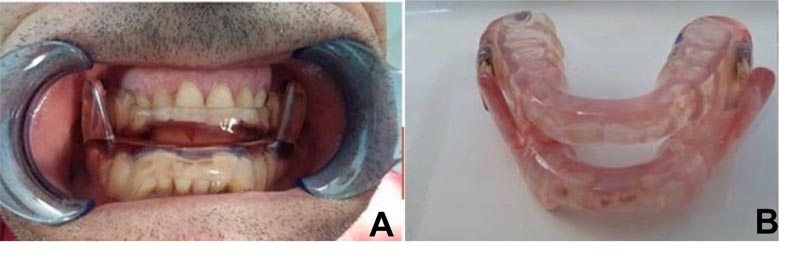

Vincenzo Ronsivalle, Federica Casella, Grazia Fichera, Orazio Bennici, Cristina Conforte and Antonino Lo Giudice

Special Issue 3: Special Issue Introduction on the Maxillofacial Rehabilitation: Biomaterials and

Techniques

Edited by: Dinesh Rokaya